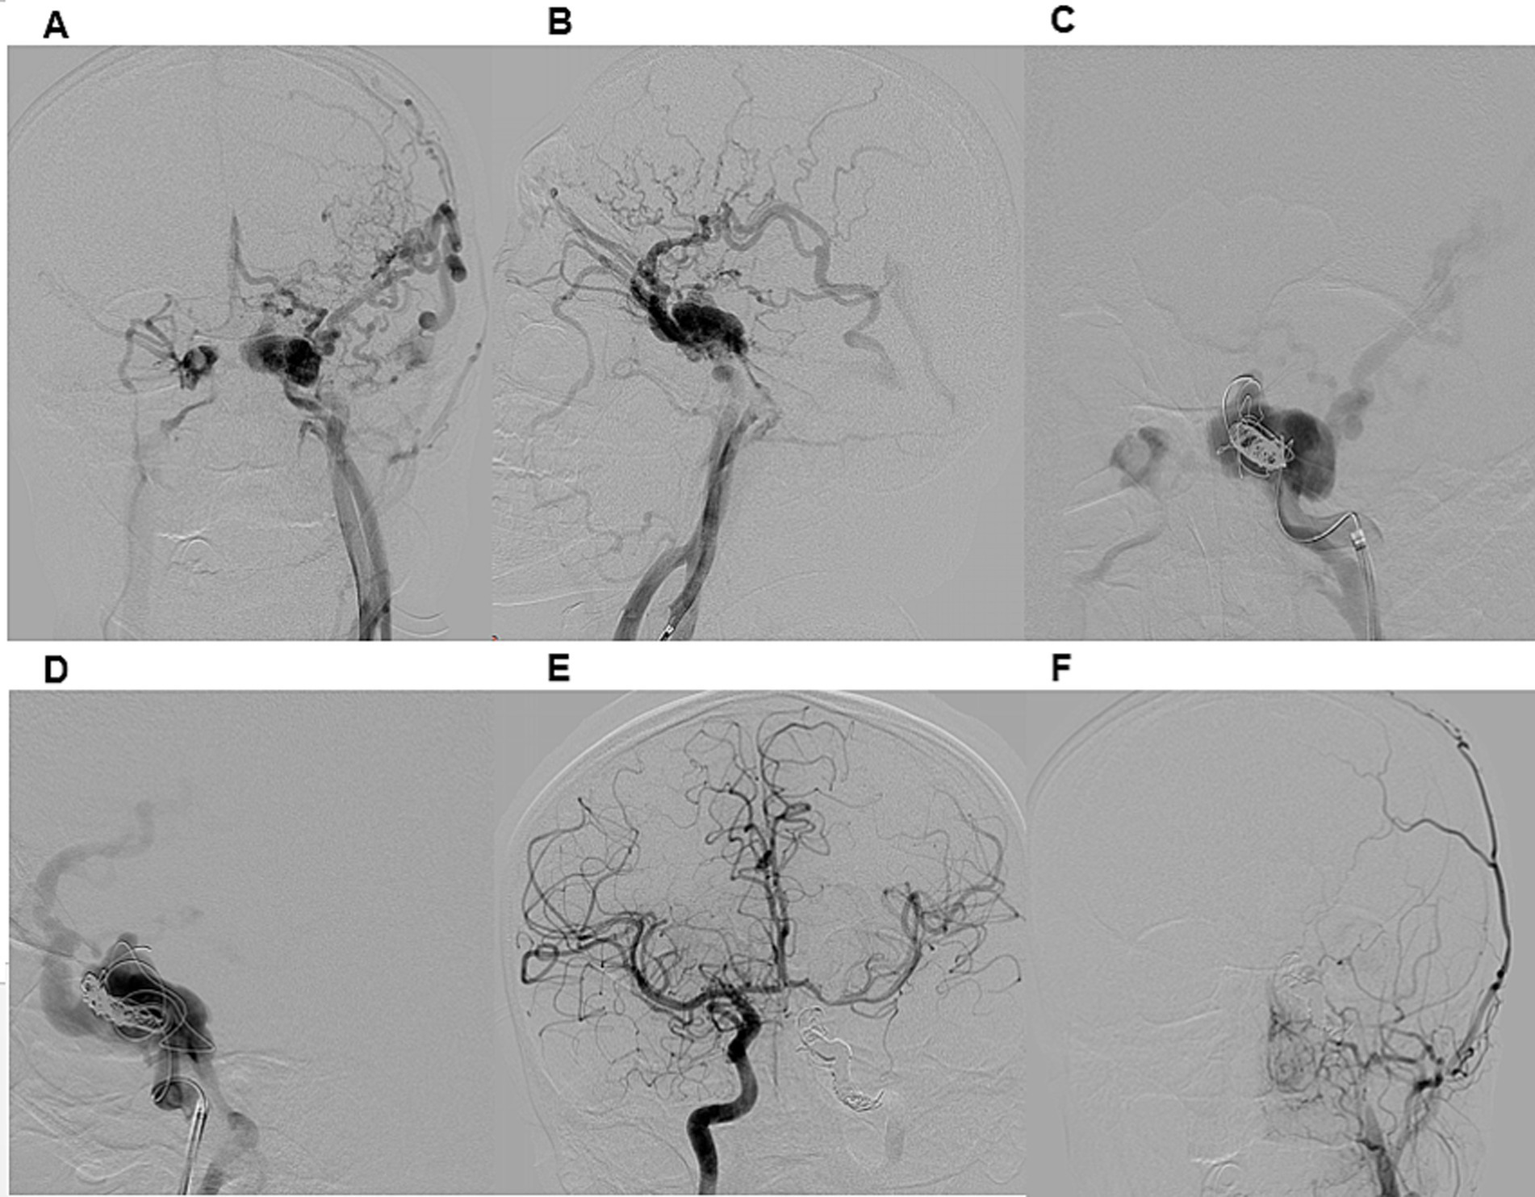

Illustrative case 2. A 21-year-old male presented with a seven-month history of conjunctival injection in the left eye, exophthalmos, and strabismus following a car accident. DSA (A,B) confirmed a direct CCF on the left side, classified as Type A according to Barrow et al. and Type 5 according to the Thomas classification system. Venous drainage was retrograde through an enlarged left superior ophthalmic vein, deep and superficial cortical veins, and the intracavernous sinus. Distal ICA flow was reduced, while both the anterior and posterior communicating artery were patent. A right ICA angiogram with compression (Matas maneuver) of the left CCA demonstrated sufficient collateral flow through the anterior communicating artery. The patient underwent transarterial embolization of the CCF and left ICA occlusion under general anesthesia (C,D). A 6F guiding catheter was introduced, and a Headway 17 microcatheter was advanced into the CCF. Embolization of both the CCF and ICA was performed using detachable coils. Post-procedural DSA confirmed complete occlusion of the left ICA and CCF (E,F). At discharge, chemosis had regressed, and at the three-month follow-up, exophthalmos and sixth nerve palsy had also resolved.

The most performed procedure was CCF occlusion via the ICA (Figure 2). Additional techniques included combined occlusion of the CCF and ICA (Figure 3), flow diverter-assisted CCF occlusion, and CCF occlusion via the superior ophthalmic vein (SOV) approach and the inferior petrosal sinus (IPS) approach.